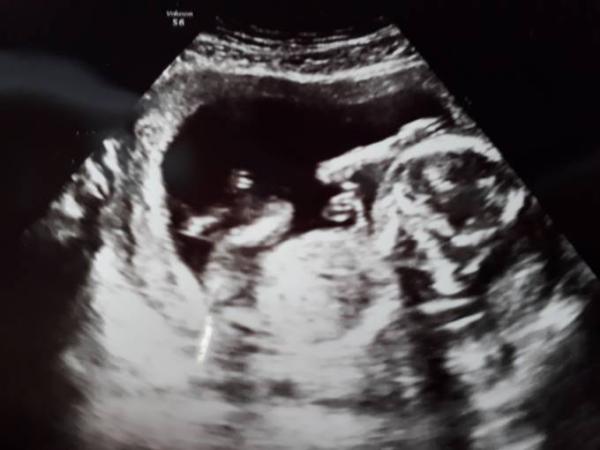

Hatte heute bei 15+2 wieder VU. Da ich noch gar kein US Bild hatte und heute eigentlich auch keiner dran gewesen wäre, hab ich mir dann doch einen Wunsch US genehmigt.

Und bin sooo froh es gemacht zu haben ich fühle mich ja immer noch so unschwanger, einfach ganz anders wie bei meinem Sohn. Klar, eigentlich ist es auch gut wenn man kaum Beschwerden hat, aber auch total komisch. Auf jeden Fall hat sich das Krümelchen fleissig bewegt und sich immer lässig mit der Hand über den Kopf gestreichelt. Total süss. Es sah alles super aus. Ca. 14 cm und 133g. Und dieses Mal liegt die Plazenta auf der Seite und nicht wie bei meinem Sohn vorne. Aber schüchtern ist es noch

es wollte weder sein Profil zeigen noch sein Geschlecht